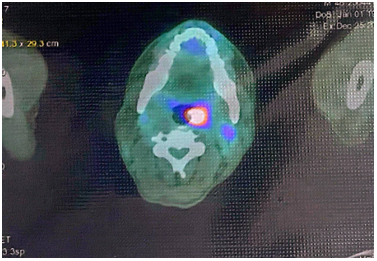

CASE LÂM SÀNG: CHẨN ĐOÁN BỆNH NHÂN MẮC HAI UNG THƯ: GIST RUỘT NON VÀ UNG THƯ TUYẾN GIÁP TẠI TRUNG TÂM Y HỌC HẠT NHÂN VÀ UNG BƯỚU, BỆNH VIỆN BẠCH MAI